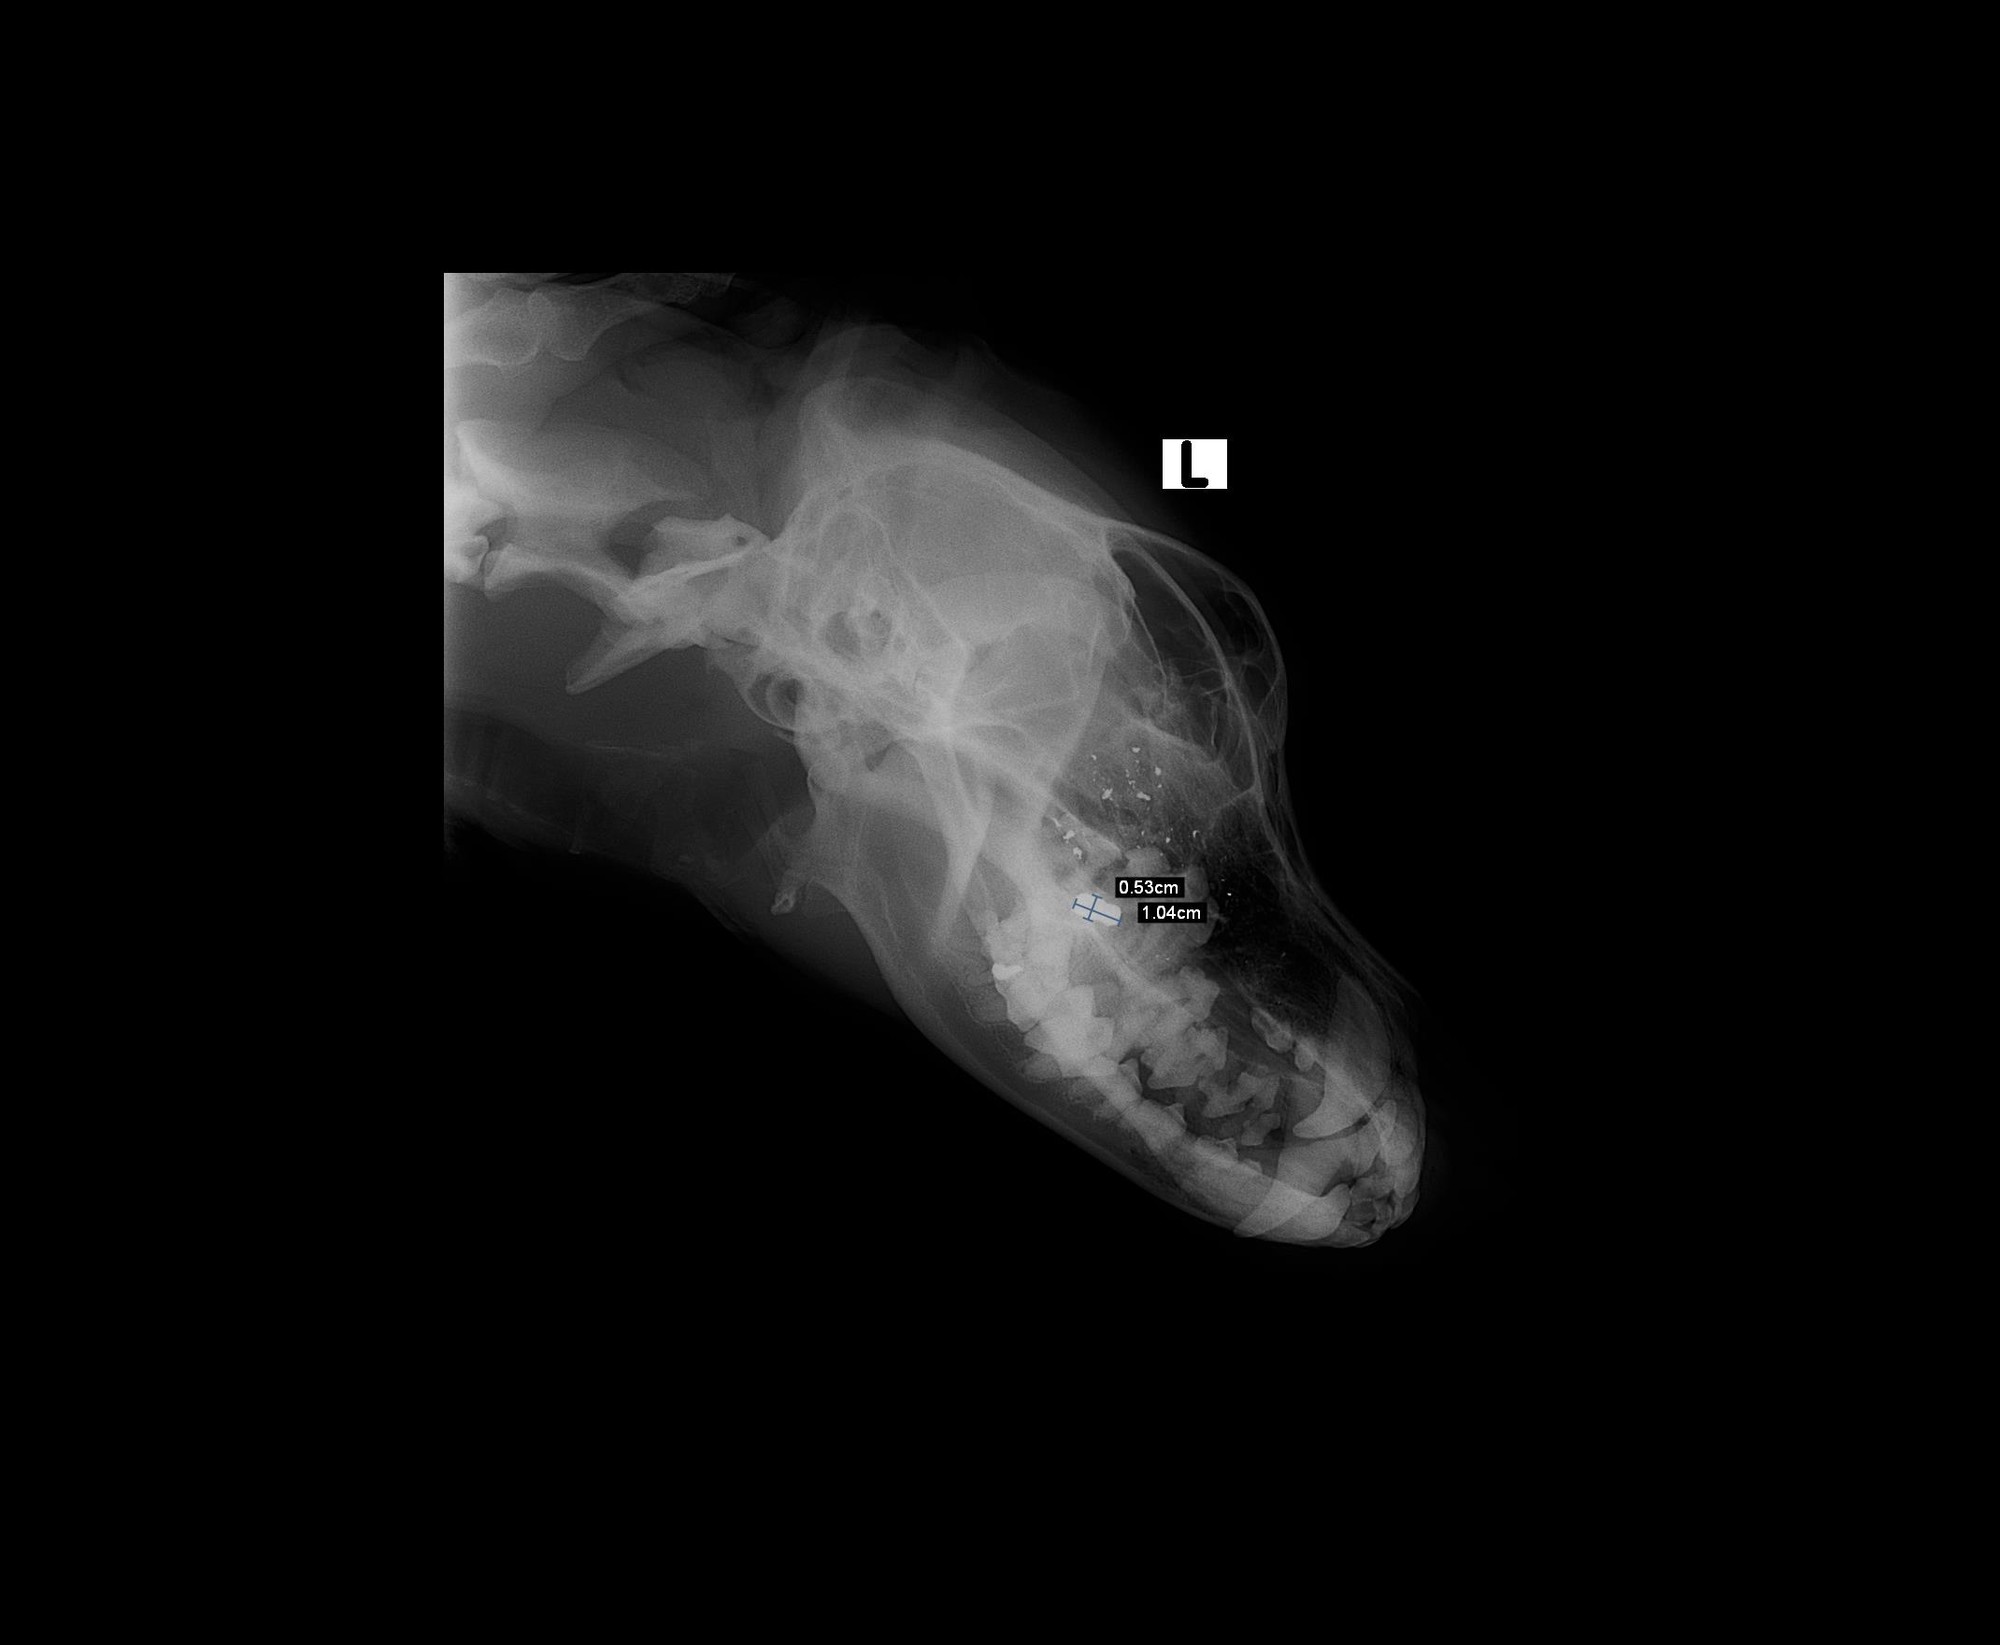

Falco je pan Úžasný. Je to neskutečně vděčný a milý pejsek. Zvyklý na děti. Ty má moc rád, vrtí na ně ocáskem. Jeho minulá rodina ho našla svázaného se zalepeným čumákem a nechali si ho. Bohužel postupem času neměla matka samoživitelka na pejska dostatek času a financí. Proto se mu rozhodla najít domov. Falco na nás působil smutným dojmem. Přišli jsme na veterině na to, že mu tlačí na zub kovový úlomek. Pravděpodobně byl v minulosti postřelen nebo měl sdrátovanou čelist. Netušíme, protože kontakt na původního majitele nikdo nemá. Falco je mírný a klidný pejsek, zvyklý na byt. Nevadí mu jiní psi, nemusí ty malé. Kočky ignoruje. Rád jezdí autem, na veterině je hodný.

• po operaci kvůli kovovému úlomku, který mu tlačí na zub - pravděpodobně byl v minulosti postřelen, měl sdrátovanou čelist